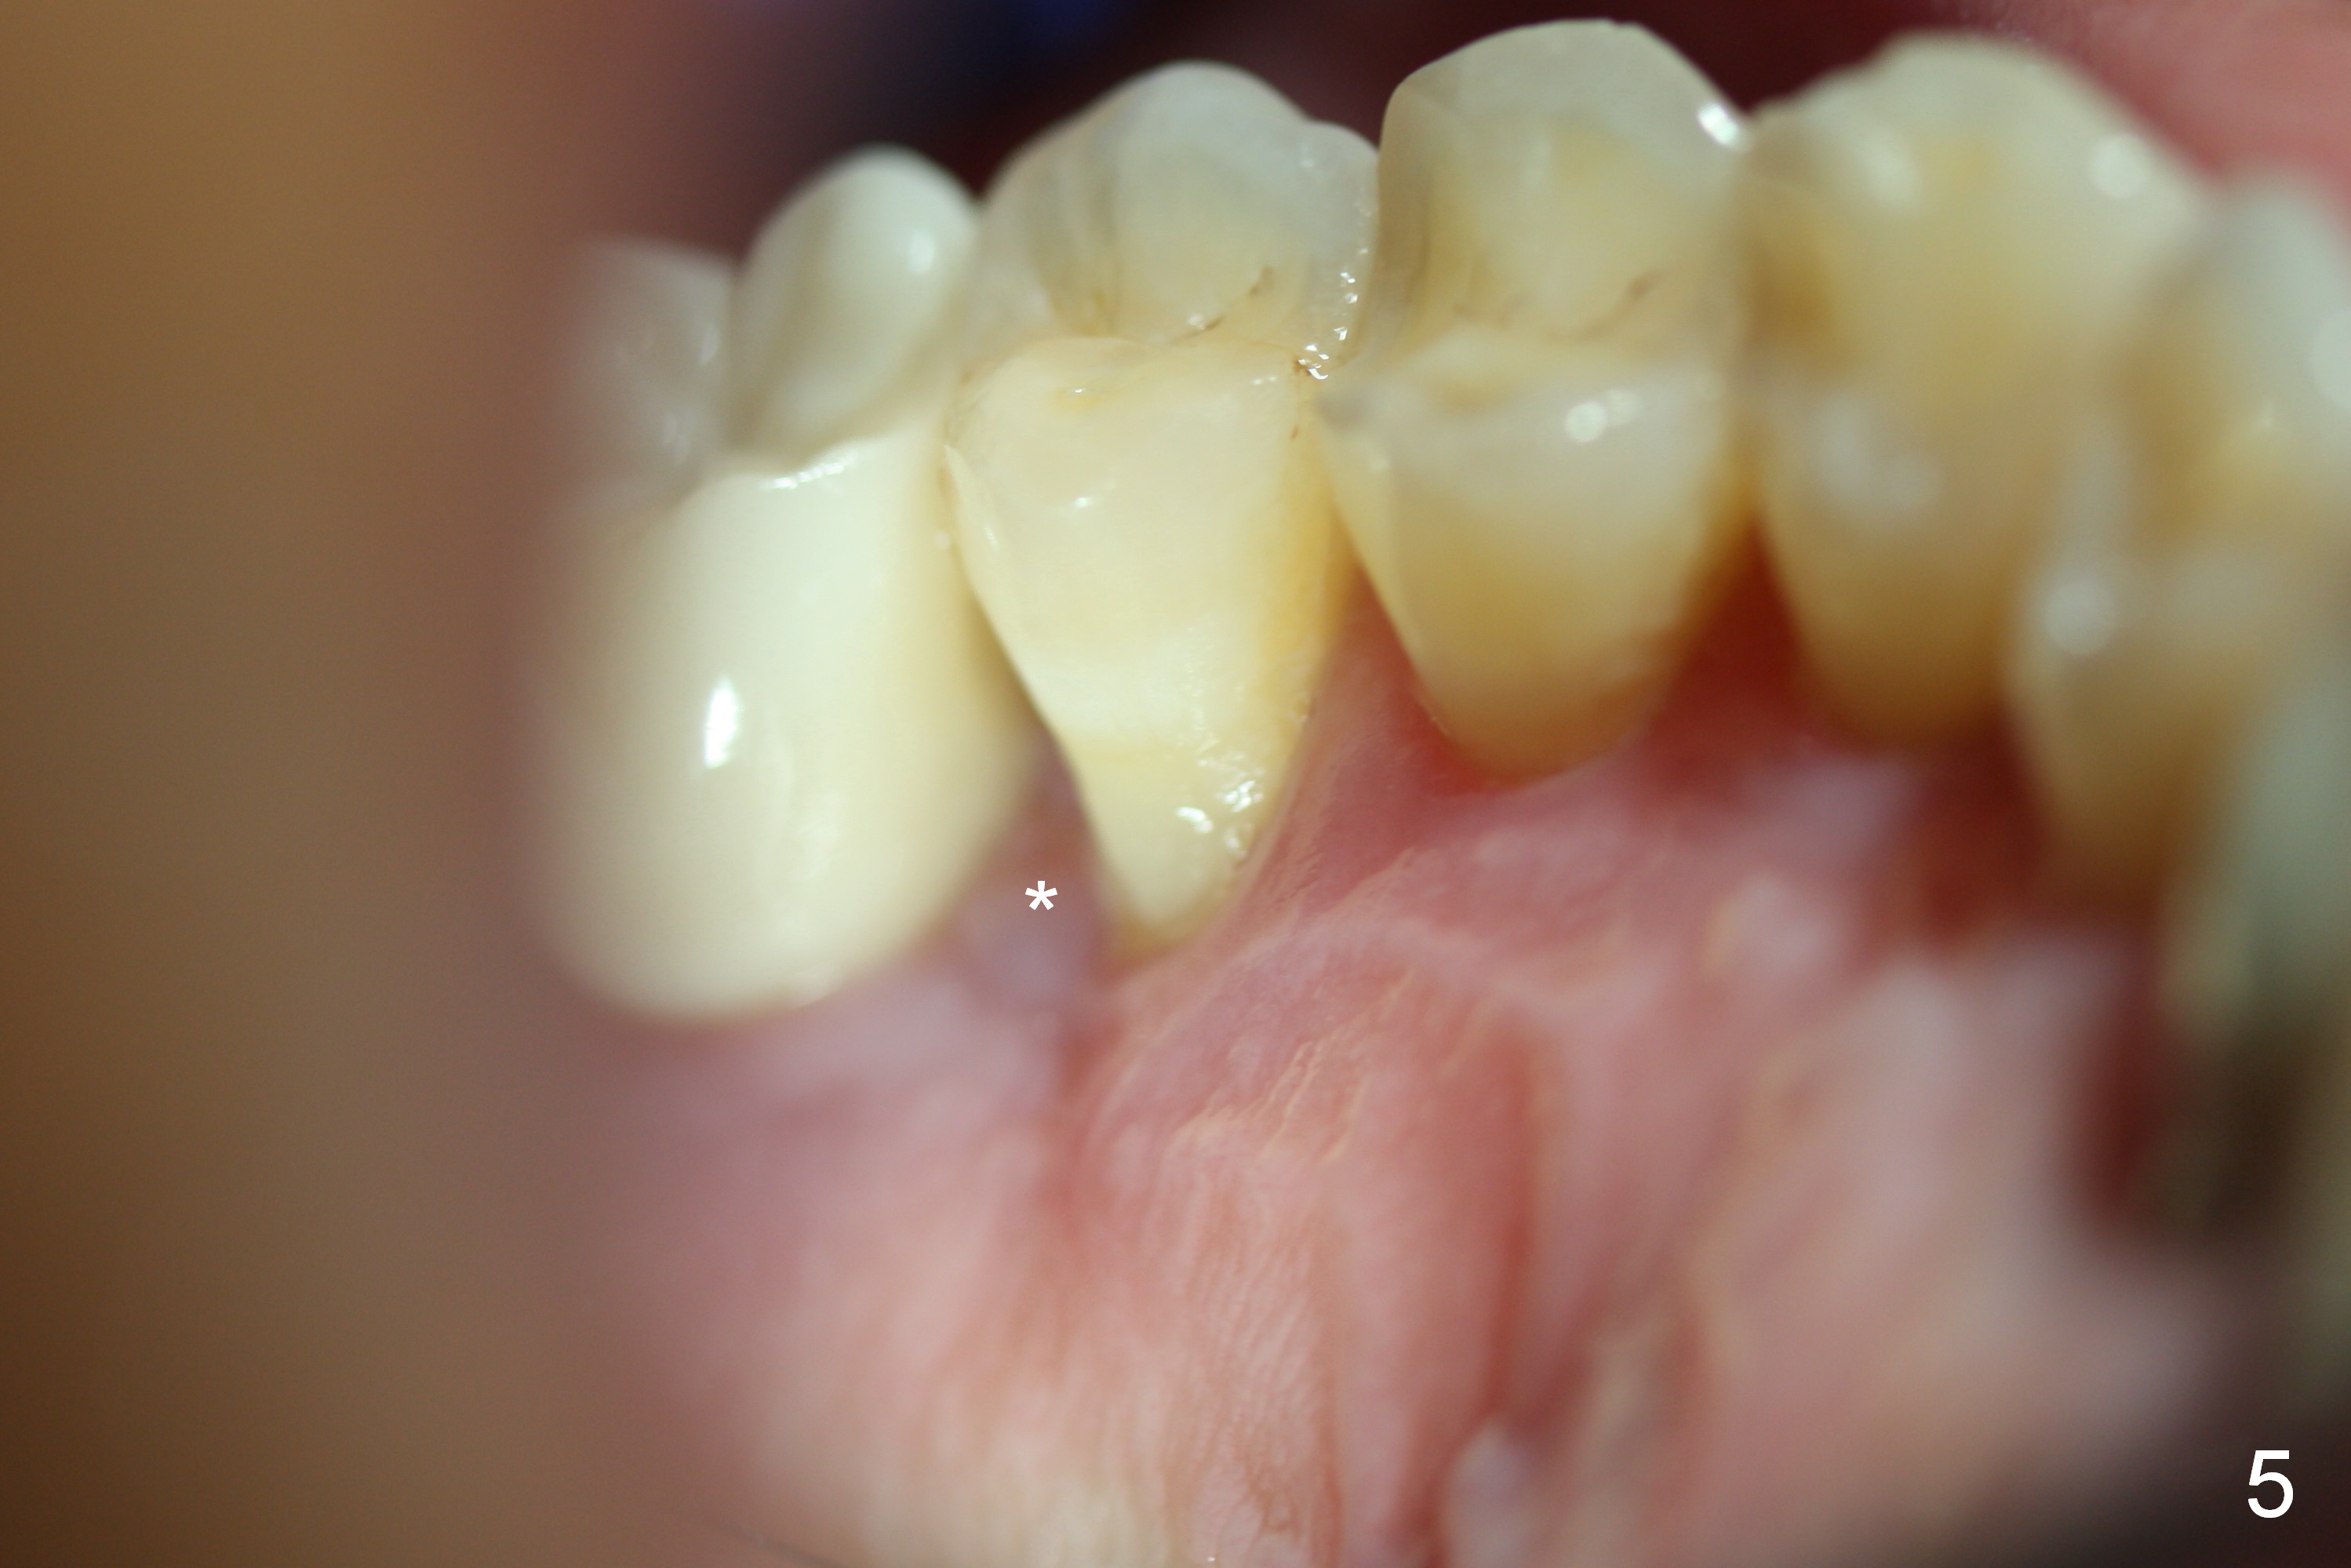

The distal buccal (Fig.1) and palatal (Fig.2) papillae (*) are recessive at the tooth #4. Following extraction and use of 3.8 mm Magic Drill, a 4.5x13 mm implant is placed lower than the mesial crest (Fig.3) to reduce the chance of the distal implant thread exposure. The latter is a measure to decrease peri-implantitis. A 4.5x5.7(4) mm pair abutment is placed (Fig.4,5). The remaining socket is filled with allograft/Osteogen placement. The large space between #3 and 4 implants is occupied by the healthy gingiva, where bone graft cannot get in.